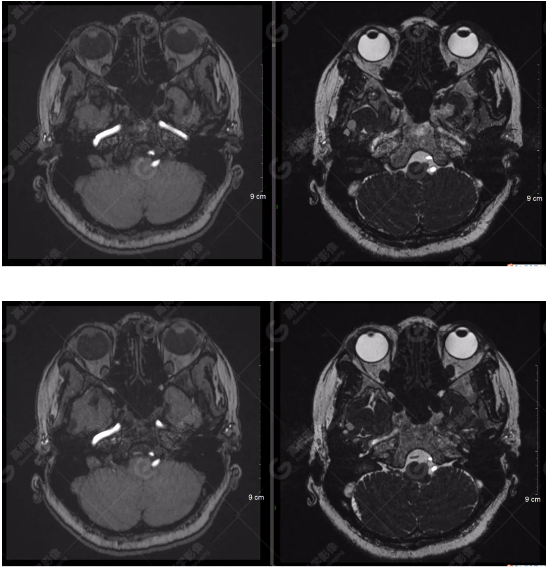

顱腦MRA及ciss序列示腦基底動脈環(huán)完整,雙側(cè)頸內(nèi)動脈末段、大腦前動脈、大腦中動脈、大腦后動脈及其主要分支顯影良好,管徑及走行正常,無明顯局灶性增粗或變細(xì)。雙側(cè)椎動脈末段沿延髓左側(cè)向上走行,左側(cè)面聽神經(jīng)輕度受壓移位,左側(cè)面聽神經(jīng)周圍見細(xì)小血管包繞。右側(cè)面聽神經(jīng)及雙側(cè)三叉神經(jīng)周圍未見異常血管影。

1.雙側(cè)椎動脈末段沿延髓左側(cè)向上走行,左側(cè)面聽神經(jīng)輕度受壓移位,左側(cè)面聽神經(jīng)周圍見細(xì)小血管包繞,可符合面聽神經(jīng)壓迫綜合征。